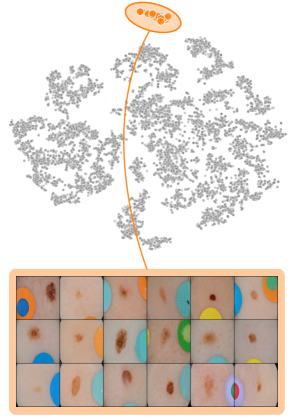

where denotes element-wise multiplication. This yields a heatmap that can be used as a soft mask or converted to a binary segmentation mask, for instance using thresholding techniques like Otsu’s method [57]. An example is shown in Fig. 2 (right), showing soft masks as heatmaps from concept-conditioned local attribution scores, along with binary masks for three known data artifacts: rulers and band-aids for skin cancer detection, and pacemakers in chest radiographs.

Notably, automated bias localization has the potential to reduce manual annotation efforts. These additional annotations can be utilized for various applications, e.g., as input for bias mitigation approaches requiring prior information on the bias to be unlearnt (see Sec. 5). Other applications include the design of metrics to measure artifact reliance or the spatial isolation of the bias to copy-paste it onto non-artifactual samples to measure the model’s sensitivity is towards the insertion of the artifact [59].

6.4 Spatial Bias Localization

To spatially localize biases in input space with CAVs, we compute local explanations for the element-wise product of latent activations and concept direction (see Eq. 2). We use the controlled artifacts, specifically timestamp (HyperKvasir) and micropscope (ISIC2019) with ground truth concept localization masks for evaluation. We compute (1) the percentage of relevance within the ground truth mask and (2) the Jaccard index, or Intersection over Union (IoU), of the binarized localization mask with the ground truth. In Fig. 9, we report both metrics using CAVs computed on different layers of VGG16 and ResNet50. The layer choice for concept representations is key, as for example middle layers perform better to localize timestamps and earlier layers are more effective to localize the microscope. In comparison with Fig.7, we find that the optimal layer for bias localization may differ from the one for sample retrieval. Interestingly, the IoU for the microscope artifact is consistently low, as models primarily focus on the border of the circle instead of the entire area, as indicated by qualitative results in Appendix A.6.3. Unlike artifact relevance, the IoU metric also measures how much of the expected areas the computed mask does not cover.